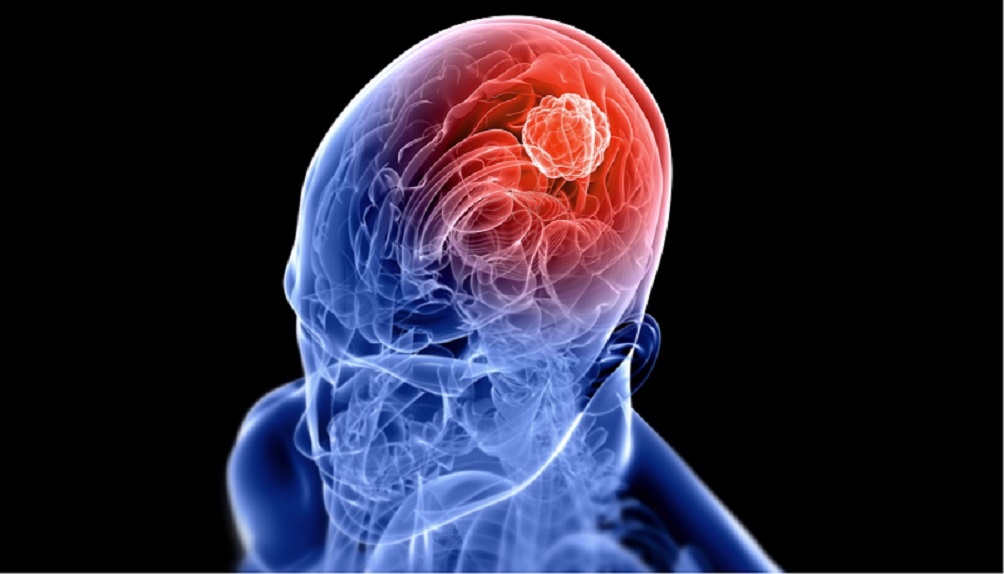

La peor forma de cáncer de cerebro, glioblastoma multiforme (GBM), es considerada en gran medida incurable por los médicos. Las víctimas generalmente mueren dentro de un año y medio después de ser diagnosticadas con los tumores.

El cáncer de cerebro, es una enfermedad tan devastadora que la Academia Nacional de Ciencias la llama “El Terminator”. Pero un innovador “ataque final” basado en la nanotecnología alrededor de las células cancerosas, por investigadores de la Universidad de Tel Aviv, podría proporcionar a los médicos una nueva forma de tratar, o incluso de curar el glioblastoma multiforme y otros cánceres malignos asesinos.